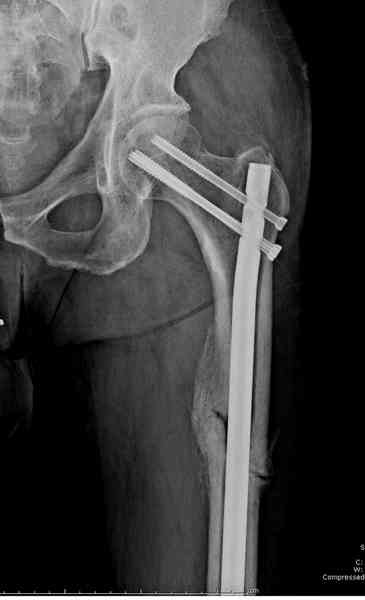

Здесь представлены снимки больного 65 лет, поступившего с диагнозом перелом

бедра после автоаварии.

В первый же день произведено антеградное штифтованием DePuy Trochanteric Nail.

На второй день (7) обнаружен пропущенный перелом,

сделаны Компьютерная Томограмма

и проведены шурурпы через и спереди штифта без удаления.

Послеоперационные снимки